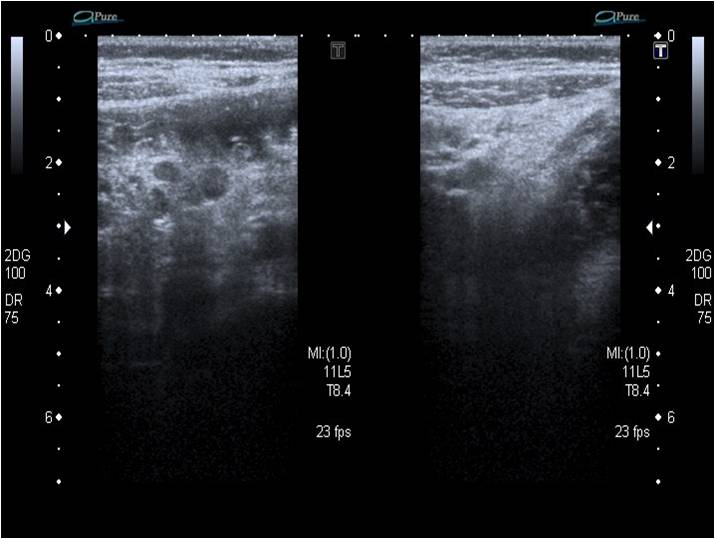

• Ecografía abdominal: hígado, vesícula y vías biliares, riñones, vía urinaria, vejiga, páncreas y bazo sin alteraciones. Las asas del intestino delgado y el colon muestran una pared de grosor normal y un discreto aumento de peristalsis. Llama la atención la hiperecogenicidad de grasa mesentérica, con múltiples y pequeñas adenopatías en su interior y un aumento de vascularización. Pequeña cantidad de líquido libre en fosa ilíaca derecha. Estos hallazgos sugieren, teniendo en cuenta información clínica, la posibilidad de enfermedad inflamatoria intestinal.